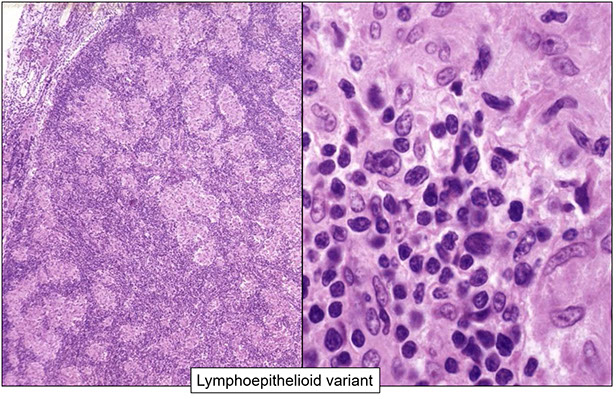

Anaplastic large cell lymphoma (ALCL), ALK positive

Anaplastic large cell lymphoma (ALCL), ALK negative